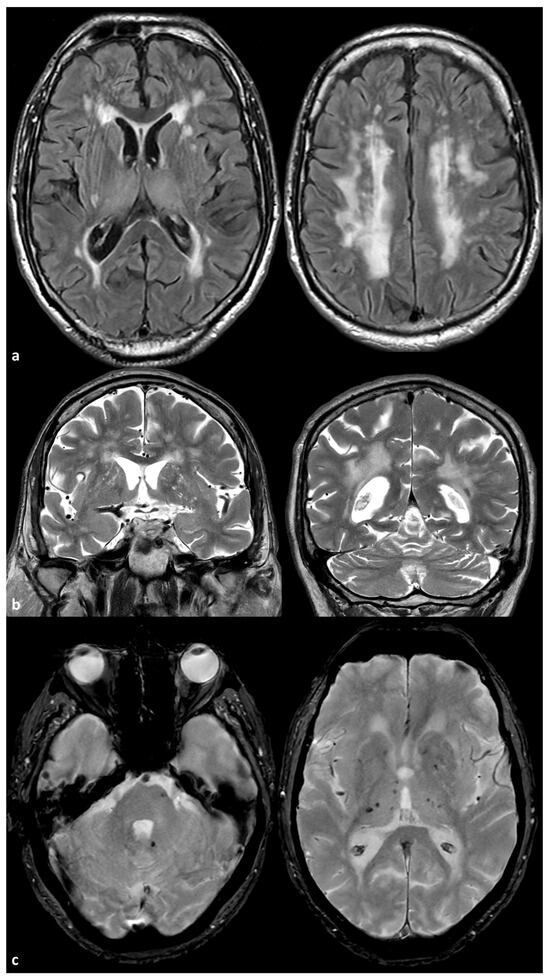

- Duering, M.; Biessels, G.J.; Brodtmann, A.; Chen, C.; Cordonnier, C.; de Leeuw, F.-E.; Debette, S.; Frayne, R.; Jouvent, E.; Rost, N.S.; et al. Neuroimaging standards for research into small vessel disease—Advances since 2013. Lancet Neurol. 2023, 22, 602–618. [Google Scholar] [CrossRef]

- Uemura, M.; Hatano, Y.; Nozaki, H.; Ando, S.; Kondo, H.; Hanazono, A.; Iwanaga, A.; Murota, H.; Osakada, Y.; Osaki, M.; et al. High frequency of HTRA1 and ABCC6 mutations in Japanese patients with adult-onset cerebral small vessel disease. J. Neurol. Neurosurg. Psychiatry 2022, 94, 74–81. [Google Scholar] [CrossRef] [PubMed]

- De Vilder, E.Y.; Cardoen, S.; Hosen, M.J.; Le Saux, O.; De Zaeytijd, J.; Leroy, B.P.; De Reuck, J.; Coucke, P.J.; De Paepe, A.; Hemelsoet, D.; et al. Pathogenic variants in the ABCC6 gene are associated with an increased risk for ischemic stroke. Brain Pathol. 2018, 28, 822–831. [Google Scholar] [CrossRef]

- Kauw, F.; Kranenburg, G.; Kappelle, L.J.; Hendrikse, J.; Koek, H.L.; Visseren, F.L.J.; Mali, W.P.T.; de Jong, P.A.; Spiering, W. Cerebral disease in a nationwide Dutch pseudoxanthoma elasticum cohort with a systematic review of the literature. J. Neurol. Sci. 2017, 15, 167–172. [Google Scholar] [CrossRef]

- Bartstra, J.W.; van den Beukel, T.; Kranenburg, G.; Geurts, L.J.; den Harder, A.M.; Witkamp, T.; Wolterink, J.M.; Zwanenburg, J.J.M.; van Valen, E.; Koek, H.L.; et al. Increased Intracranial Arterial Pulsatility and Micro-vascular Brain Damage in Pseudoxanthoma Elasticum. AJNR Am. J. Neuroradiol. 2024, 45, 386–392. [Google Scholar] [CrossRef]